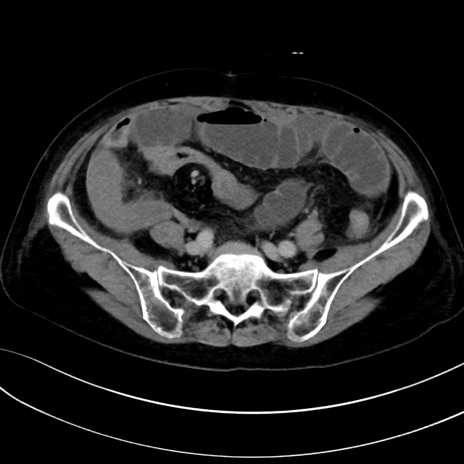

症例13 CT(横断像)1日半後